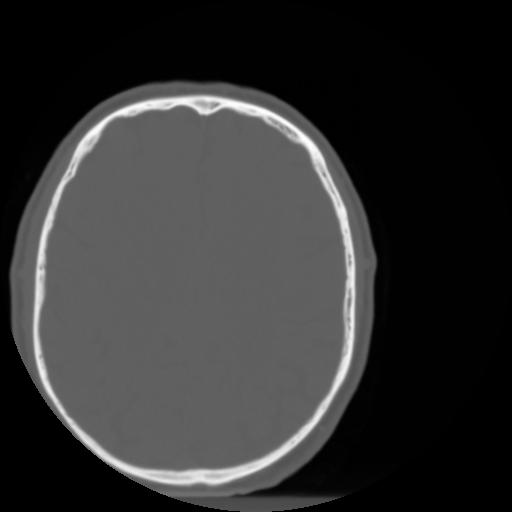

3 CEREBRO,,Axial,3.0,CEREBRO,,